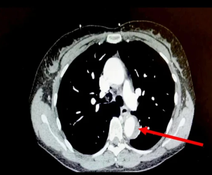

Doctors diagnosed the woman with a leak in her aorta, which is medically known as acute aortic syndrome or AAS. However it didn’t stop there, and specialists found that she’d experienced an aortic intramural hematoma which has a fatality rate of 40 per cent.